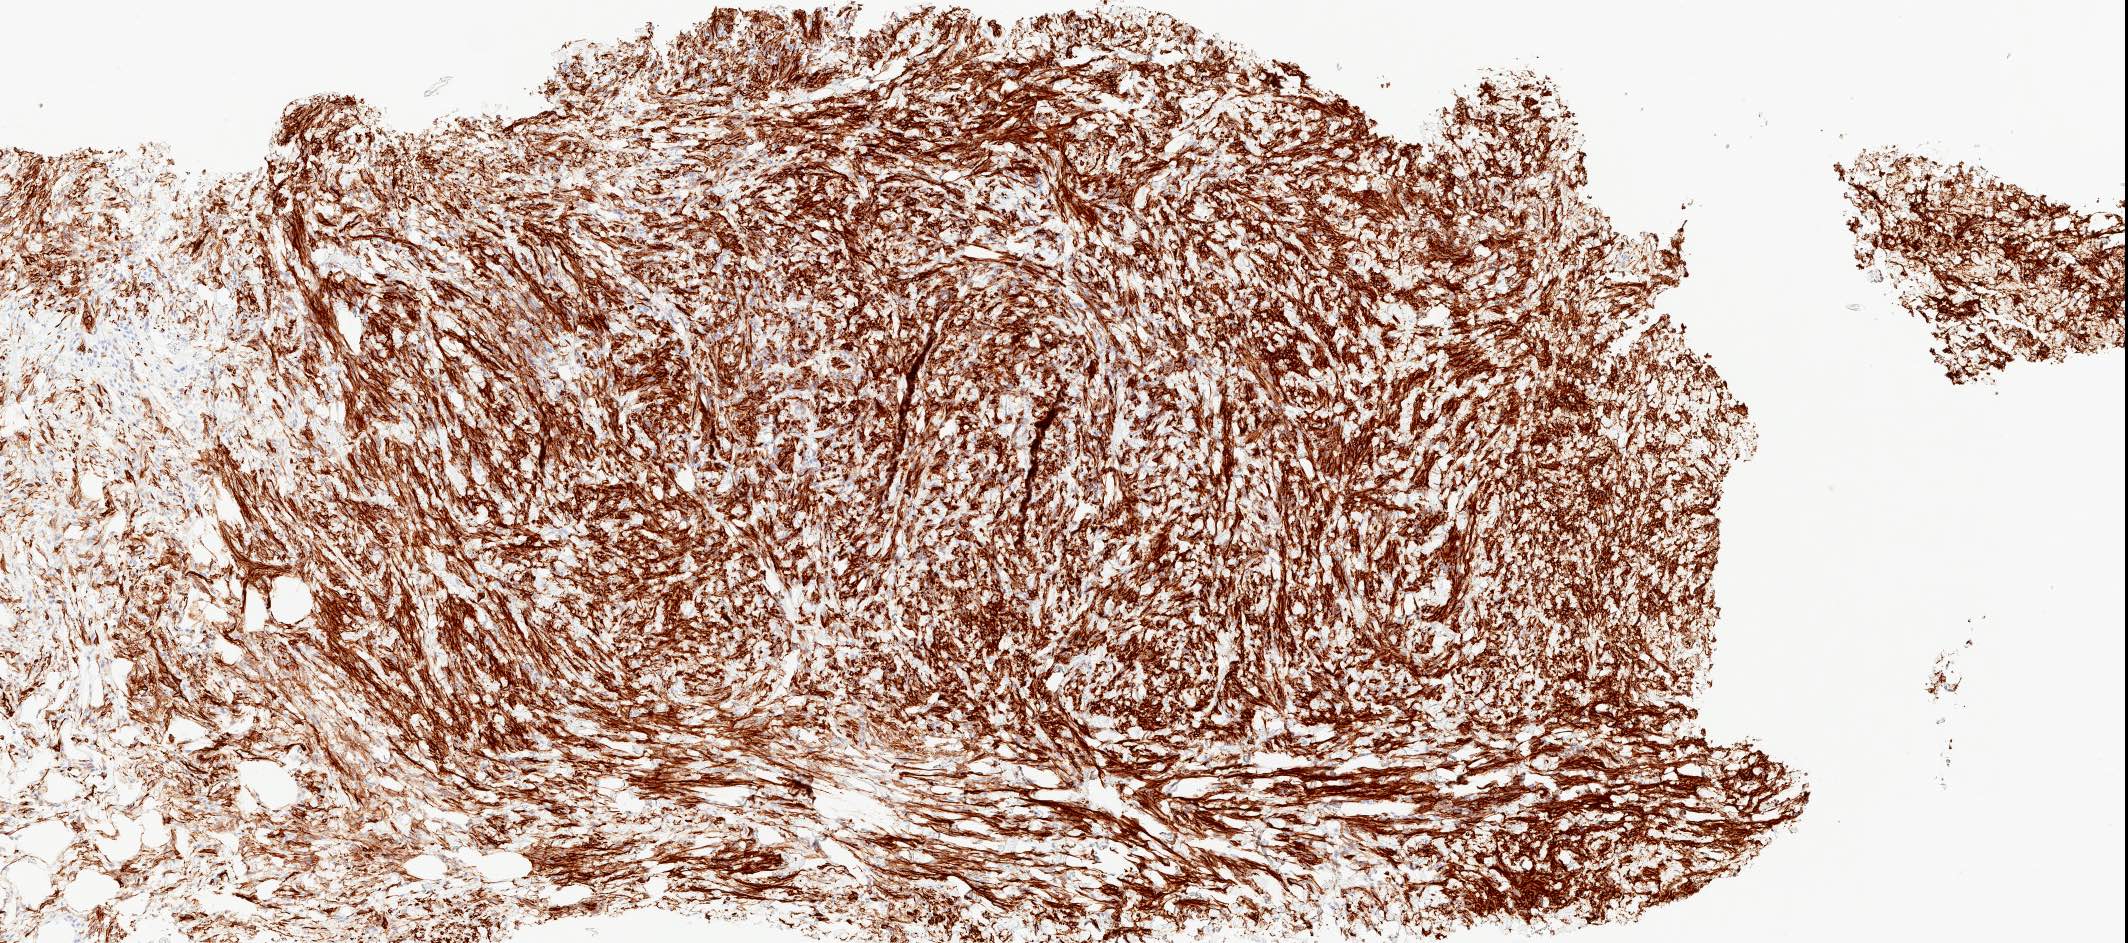

Microscopic (histologic) images

Positive stains

- Desmin (91%), vimentin, ER, PR, AR, BCL2, CD10, CD99 (Histopathology 2000;36:515, Virchows Arch 2007;450:727)

- CD34 (89%) diffuse and strong characteristic but may uncommonly show absent / focal expression (Am J Surg Pathol 2016;40:361, Breast J 2018;24:55)

Microscopic (histologic) description

- Well circumscribed, lacks true capsule, rarely infiltrative

- Bland, uniform, short to elongated spindle cells arranged as short haphazard intersecting fascicles admixed with bands of hyalinized, brightly eosinophilic collagen and variable amounts of fat